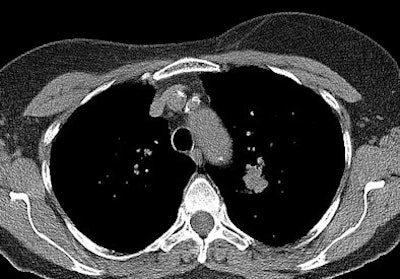

The NLST has shown that lung cancer death rates can be reduced by 20% when a high-risk group is screened with a low-dose CT scan compared with chest radiography. The participants were asymptomatic persons ages 55 to 74 who had smoked at least 30 pack years in their lifetime. Participants received a baseline CT scan and two annual screening CT exams, and were then followed for a median of 6.5 years. Screening of high-risk individuals led to a better opportunity for curative treatment, the investigators found.

"There are many potential advantages of CT screening," Heuvers pointed out. "Low-dose CT is not only a valuable tool to detect lung cancer at earlier stages, it can also be used to monitor other causes of morbidity and mortality in heavy smokers, such as ischemic heart disease and chronic obstructive lung disease (COPD). Early detection of coronary artery calcification could be used to identify patients who are likely to experience ischemic heart disease. In addition, early detection of COPD could signify patients with a rapid progression of their COPD, leading to an intensive treatment."